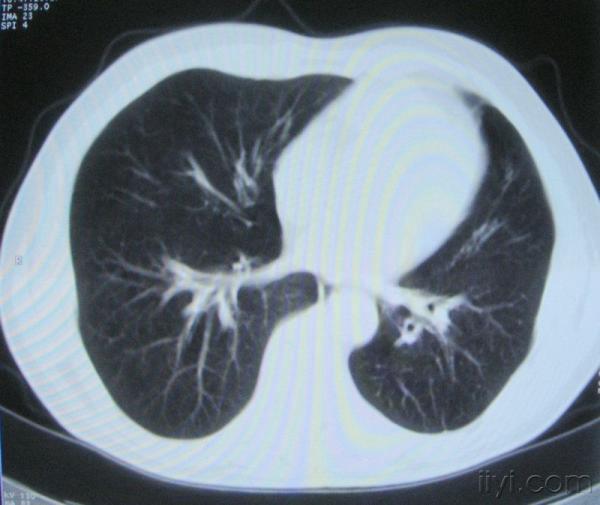

男。60岁,胸片示支气管炎治疗后复查CT。

你指那个肯定是淋巴结,中央系坏死,这很常见,特别在双侧腹股沟会经常看到。这个双侧腋窝及纵隔见多发小淋巴结征。

根据位置考虑应该是淋巴结,密度不均,是因为肿大的淋巴结中心液化坏死